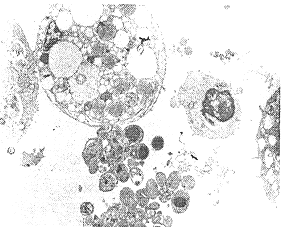

2.1 电镜观察 透射电镜可见DCs伸展的突起,胞浆中富含线粒 体,较少溶酶体,并 可见凋亡物质(凋亡小体)(见图1);扫描电镜还拍摄到DC正在捕捉凋亡小体(见图2);γ-射线照射促使胆管癌细胞发生凋亡并释放凋亡小体(见图3)。

图1 透射电镜显示树突状细胞吞噬的凋亡小体(×7600)?jkv&, 百拇医药

Fig1 Transmission electron microscopy revealed apoptotic material and body of apoptotic cell within the cytoplasm of glutaraldehyde-fixed DCs

图3 透射电镜显示胆管癌细胞发生凋亡形成凋亡小体(×7600)

Fig3 Transmission electron microscopy revealed that he-patochlangioma cell had finished apoptosis(programmed cell death)(×7600)\ezt, http://www.100md.com